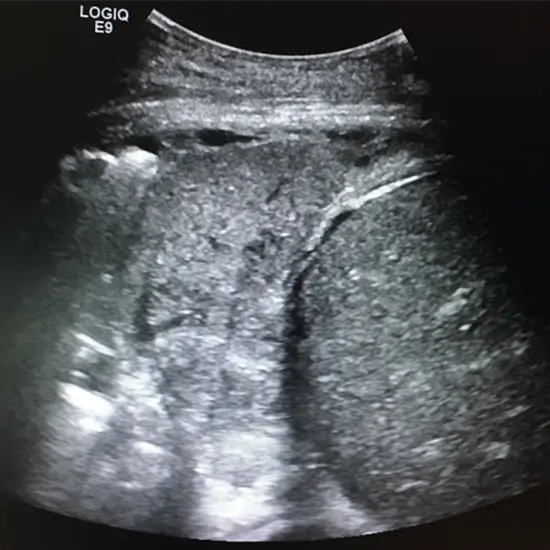

A thoracic ultrasound, often known as a chest ultrasound, is a diagnostic procedure that produces precise images of the chest. Ultrasound technology creates images of your organs using high-frequency sound waves and echoes.

The ultrasound Thorax test is performed at a healthcare facility, patient will be kept flat on the table for examination. A device called a probe or transducer is moved over the chest area for the examination and the gel is used for smooth and good test-quality images. The procedure gives a detailed view of the chest/ thorax. Ultrasound produces the pictures and gives an examination of the chest in detail.